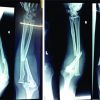

Intraoperative fluoroscopy images proved the radial head reduction and ulna fracture to be stable. Then, we applied a long arm splint and end the operation. Post-operative X-rays showed successful reduction of both bone fractures along with the radial head (Fig. 2).

His splint has removed 3 weeks after operation and active motion was allowed thereafter. Post-operative radiographs were obtained in 2nd week, 4th week, and 2nd month. No displacement has been noticed in follow-ups. In the 8th week of operation, intramedullary K-wire was removed intraoperatively (Fig. 3). His elbow and wrist movements showed no restrictions. There were no sensory or motor deficits.

We discharged the patient on the day after surgery. We followed him for 12 weeks. At the 8th week, intramedullary K-wire has been removed. The examination on 12th week shows no restriction in elbow movements (Fig. 4).